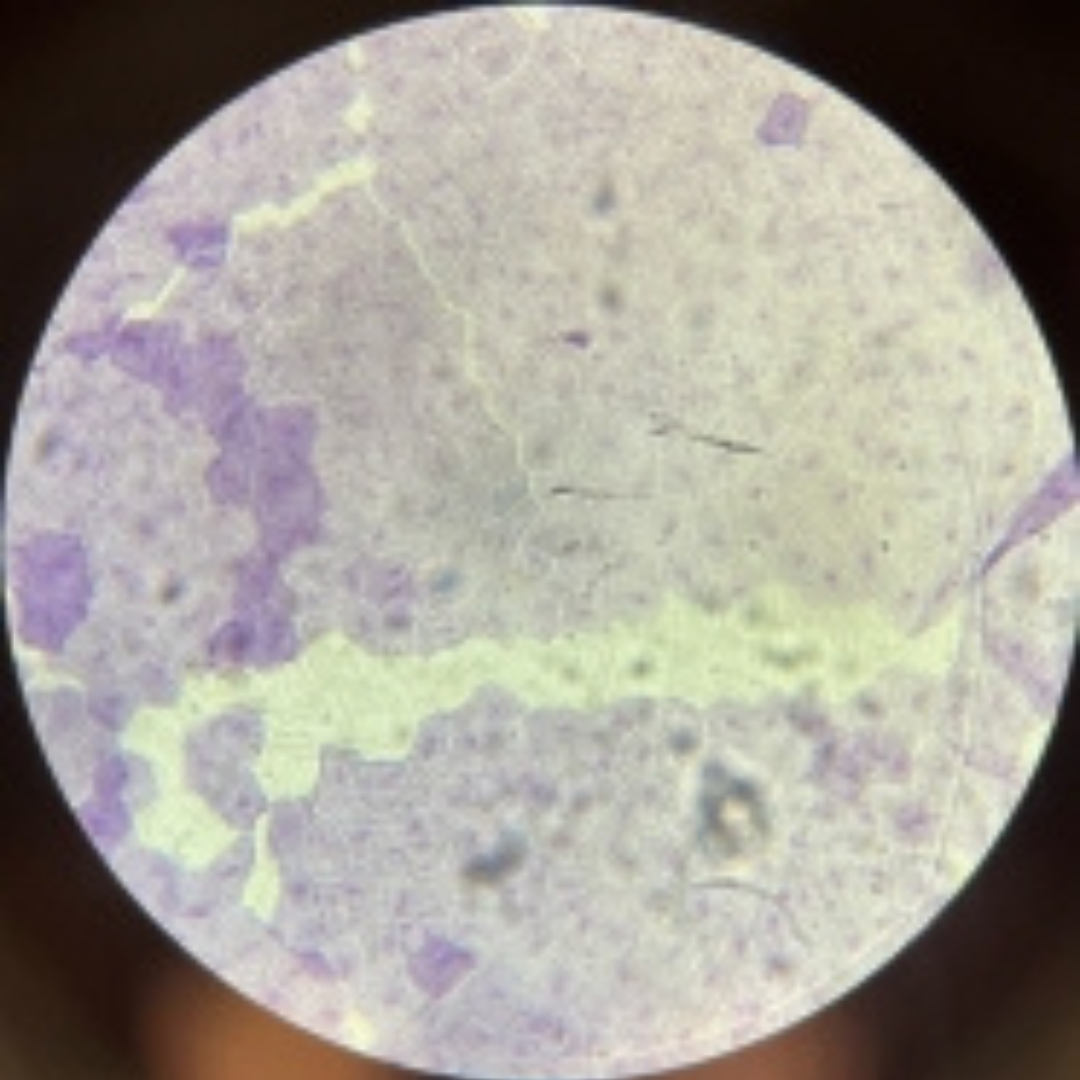

Urinary Bladder (Bladder)

Urinary Bladder (Bladder)

Urinary Bladder (Bladder)

Urinary Bladder (Bladder)